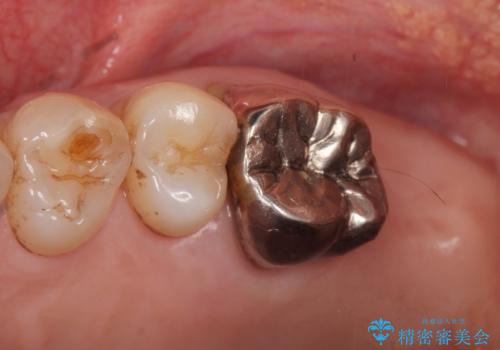

患者様のご希望により抜歯してインプラントによる治療を行いました。

上顎洞が近接しており上顎骨の厚みが薄いことから、ソケットリフト(上顎洞底挙上術)をインプラント埋入と同時に行いました。